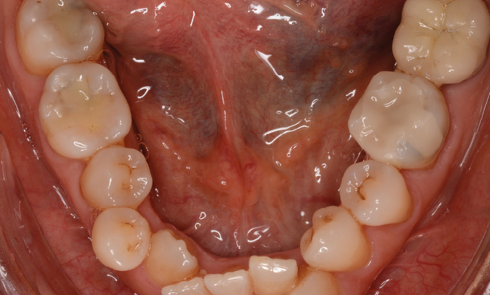

Présentation du cas (fig. 1 à 9) Madame J, âgée de 49 ans, nous est adressée par son occlusodontiste pour...